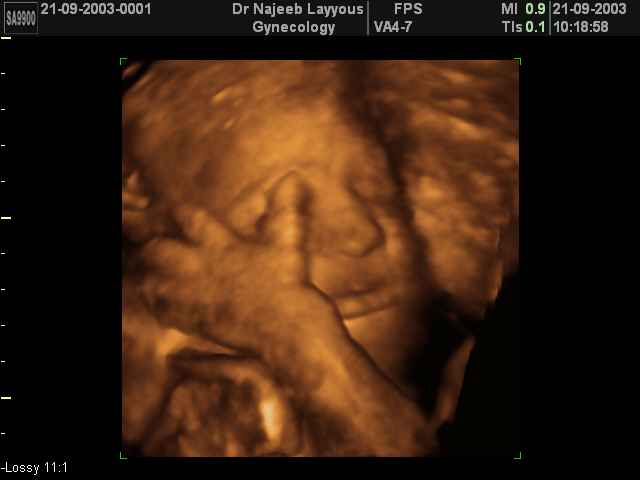

3D Fetal Face Ultrasound Scan Photos